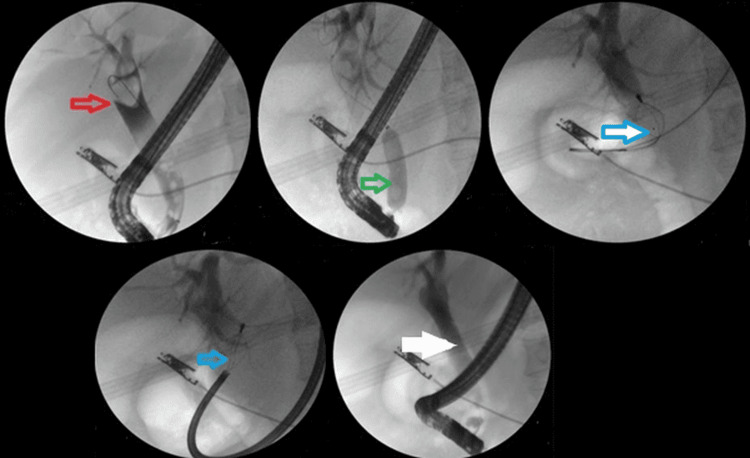

The addition of ML to EPLBD and endoscopic sphincterotomy resulted in an overall success rate of 625/682 (91.6%). Figure 3 illustrates ML used in a patient. The addition of ESWL (Figure 4) resulted in an overall success rate of 638/682 (93.5%), and the addition of EHL resulted in an overall success rate of 650/682 (95.3%) for the endoscopic removal of stones (Figure 5).

While EPLBD is effective for three-quarters of large CBDS, certain complex cases still require lithotripsy. These include large stones, stones lodged in narrow ducts, and intrahepatic stones. Due to the prohibitive cost of peroral cholangioscopy-assisted lithotripsy, ML is a practical alternative in resource-constrained settings [ref. 4]. ML utilizes a mechanical shearing force to fragment stones, leveraging a specialized apparatus comprising a basket, traction wire, and metal sheath. Two distinct systems are available: an extra-duodenoscope setup, employed at our institution for emergencies and retrieving entrapped baskets, and an integrated through-the-scope configuration, not available at our center [ref. 22–ref. 24]. ML is typically reserved for challenging stones, with a success rate of 79-94% and a complication rate of 3.3-17.6% [ref. 25–ref. 27]. Effective patient selection is paramount, with optimal candidates presenting with sizable (>1.5 cm) and hardened stones inducing substantial biliary obstruction. The existing data underscores ML’s impressive efficacy (90-95%) and favorable safety profile [ref. 4,ref. 22–ref. 24]. Our institution’s experience corroborates these outcomes in managing recalcitrant CBDS.